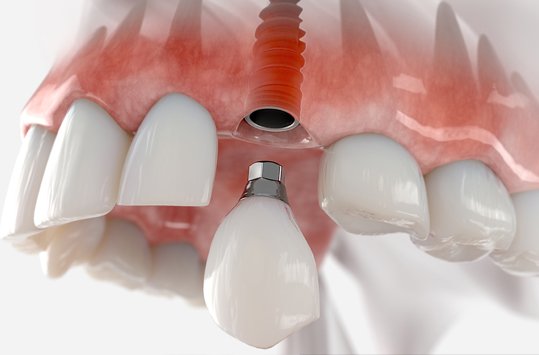

Implants are screw shaped that is placed in jawbone to replace a missing teeth. A crown is placed on this screw to look and function as the crown portion of the natural tooth. Dental implants are made majorly out of titanium material that suits the human body properly.